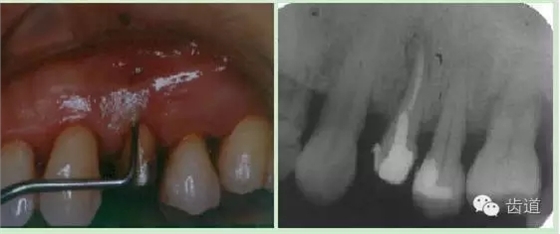

頰側牙齦相應于根中部可見瘺管,周圍齦腫脹,輕壓少量溢膿。

瘺管處尖探針探入可達根面,略有粗糙感。

PD 頰側正中10mm,窄而深,袋口緊,附著喪失9 mm。探與瘺管相通,鄰面及腭側PD 3-4 mm,樁核冠,未粘合,正中咬合輕度早接觸。松動 Ⅰ°全口口腔衛(wèi)生較差,PLI: 2,牙石(++)

875 78 缺失 彩幻及X片: